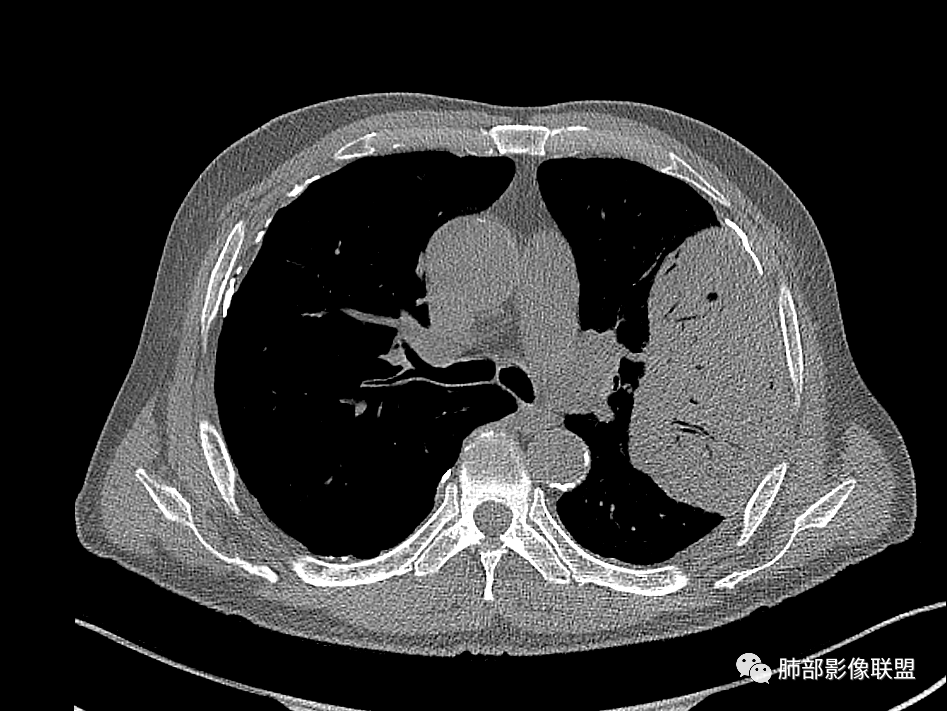

老年男性左肺团块状占位,首先会考虑肉瘤/肉瘤样癌,其次大细胞肺癌,最后不排除肺结核。

老年,明显消瘦,左侧胸廓轻度缩小?胸膜增厚,见钙化,以前结核?接触其他?整个肿块膨隆,坏死不明显,支气管通畅,轻度扩张轻度强化,考虑恶性,淋巴瘤可能

左肺上叶胸膜下肿块,膨胀性生长,边界清晰,密度不均部分坏死,未见强化,病灶内支气管迂曲扩张,病灶长轴与胸膜平行,胸膜下脂肪间隙存在,胸膜钙化,考虑放线菌?毛霉?鉴别淋巴瘤

糖尿病史,慢性病程,左肺巨大肿块,跨叶生长,肿块近端可见充气支气管征及悬浮气泡,轻度圴匀强化,病变长轴与胸膜平行,炎性标志物正常,考虑放线菌,其次淋巴瘤

老年男性,糖尿病病史,消瘦、乏力三个月,肿瘤标志物高。左肺上叶胸膜下肿块,边界清晰,可见支气管影及坏死区,增强病灶边缘强化,内部未见明显强化,邻近胸膜有累及,考虑恶性,建议穿刺活检。

左肺紧贴胸膜巨大肿块,跨叶裂生长,密度均匀,边缘清晰,内支气管略扩张,增强见血管影,强化不明显,胸膜栽赃,钙化,考虑淋巴瘤。

1)部位:周围型或中央型软组织肿块,以周围型为多见,且肿瘤多位于肺上叶。如本例:该肿瘤位于左肺上叶。

2)大小及形态:由于本病恶性程度高,早期症状不明显,发现时肿块均较大。如本例病变巨大。

3)肿块边界和边缘:多较清楚,呈圆形、类圆形,且由于肿块生长速度不均匀,可见分叶,毛刺少见。有报道肿块周围毛玻璃影是多形性癌特征表现。